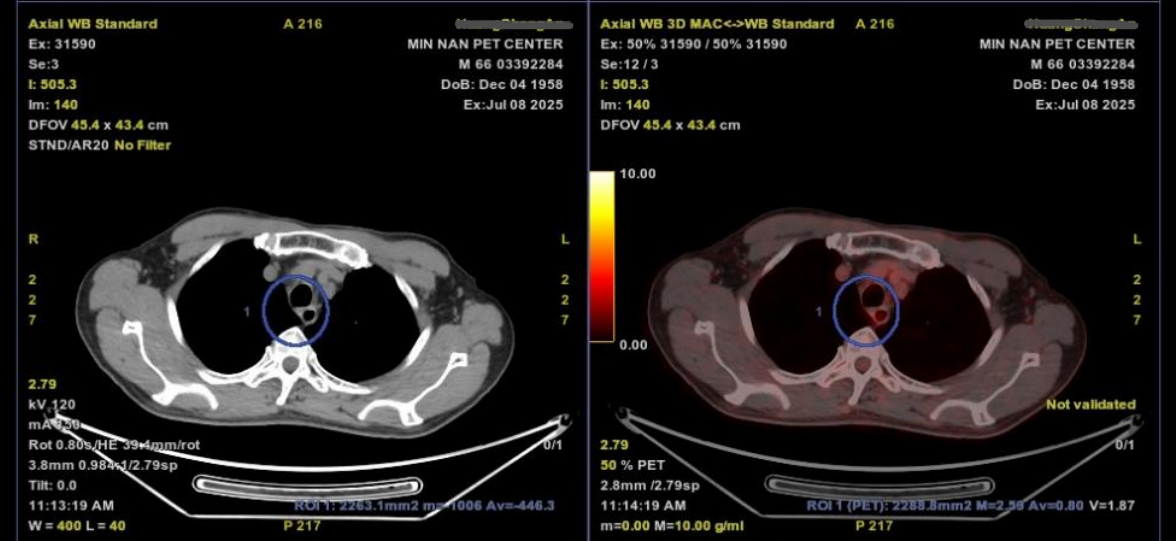

2025年2月15日,电子胃镜:距门齿约19~26cm见隆起新生物,中央糜烂溃疡,考虑食管中上段CA。

图片13.png图1 胃镜